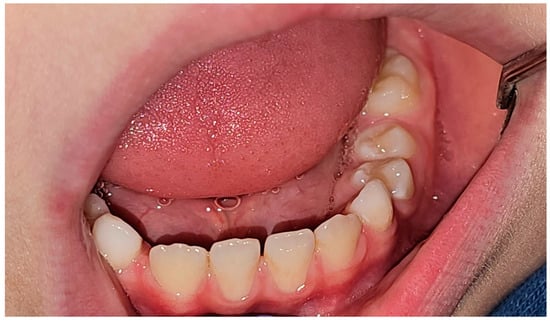

2. Case Report